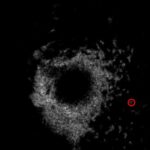

Validating a Dual-Threshold Peak Detection for Calcium Signals Around Laser-Induced Epithelial Wounds

A comparison between an automated method of collection calcium peaks to a manual version to determine the accuracy of the automated system and gain insight into the role of calcium during the wound healing process.

Posted by John Lee on Wednesday, December 23rd, 2020 in May 2020, Calcium Signals, Peaks Detection